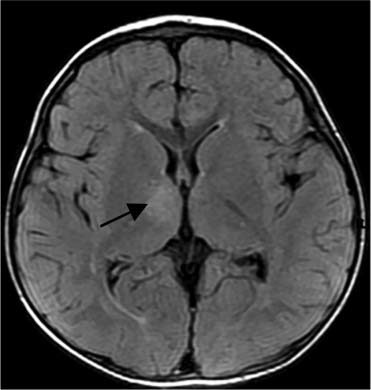

El Hallazgos en Resonancia Magnética en dos niños con mielitis que semeja un cuadro de poliomielitis producido realmente por el Enterovirus 71.

En uno la lesión estuvo ubicada entre C2 a C5 y en el otro entre T11-T12,

La RM mostró áreas de alta señal unilateral en cuerno ventral de la médula espinal.

Médula cervical. Lesion unilateral del cuerno ventral izquierdo, similar a Poliomielitis.

RM, en T1, imagen lineal hipointensa C2-C5, 2da en T2 de alta intensidad de señalAfeccion medular toracica T11-T12, ventral unilateral izquierda, lo podemos denominar el Signo del Buho tuerto.

RMN T2 corte transversal: Hiperintensidades de señal en cuernos ventrales de Médula espinal

T2 FLAIR lesiones subcorticales en Frontal derecho y Parietal izquierdo.

Puede detectarse algunas veces participación de la raíz ventral.En sus 10 pacientes con PFA, la afección de la médula espinal bilateral estuvo presente en 9 pacientes por lo tanto sólo en un caso fue unilateral.

La afeccion específica ventral de la médula espinal pueden ayudar en el diagnóstico diferencial de otros tipos de enfermedad de la médula espinal como la mielitis transversa.

Todas las lesiones ubicadas en el cuerno ventral de la médula espinal tenían un realce heterogéneo. La intensidad anormal puede estar relacionada con edema citotóxico, que puede confirmarse por RM con DWI.

Observarón una lesión Talámica unilateral